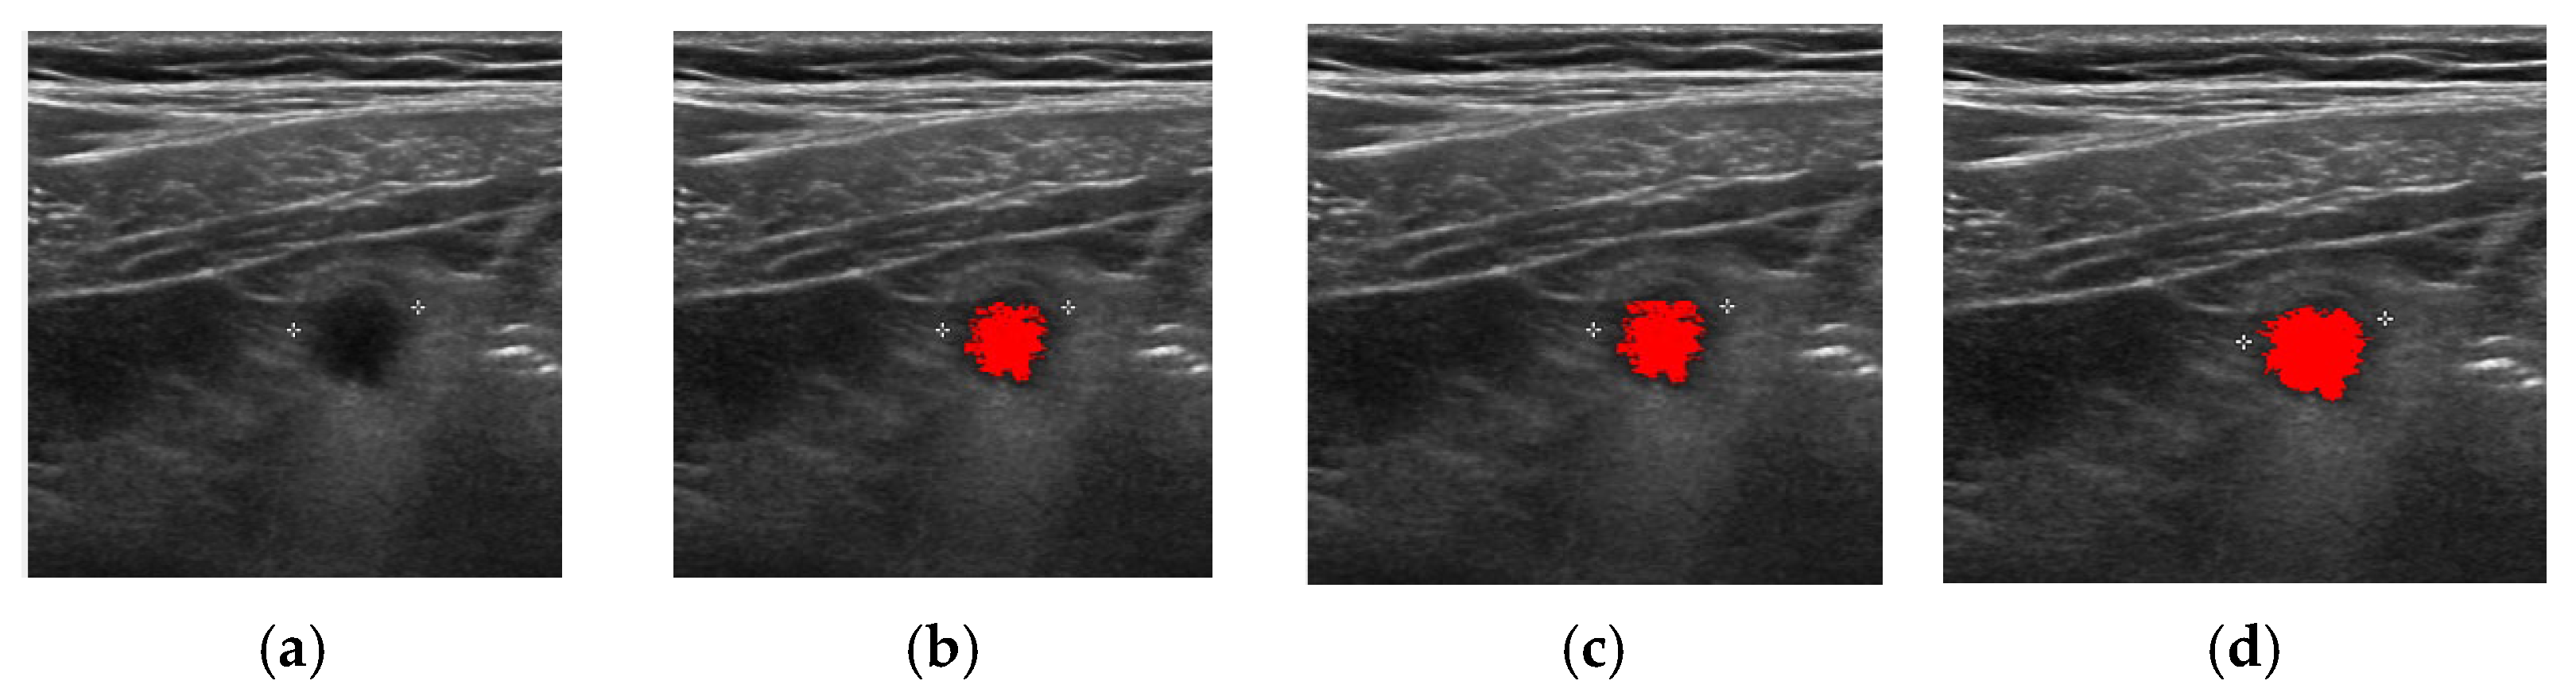

| Method | Successful Images/Total Images |

|---|---|

| FCM | 83/100 |

| ORFCM | 88/100 |

| DFCM | 91/100 |

| DORFCM | 98/100 |